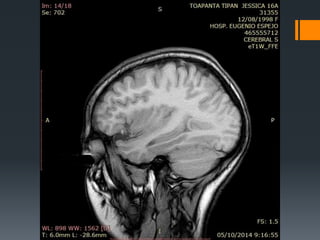

 TC SIMPLE DE CRANEO (30-09-2014)

 RESONANCIA DE CEREBRO (05/10-2014)

RMN

Donde se encuentra la lesión??

Intra-axial

Extra-axial

Supratentorial

infratentorial

Localización

anatómica

INTRAAXIAL